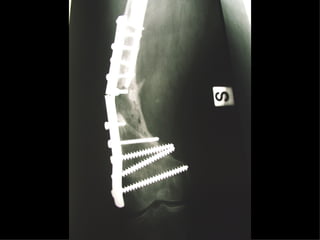

The GOTFRIED plate

La placca a compressione percutanea (PC.C.P.) di Gotfried è un mezzo di sintesi studiato per assicurare un “impattamento controllato” delle fratture pertrocanteriche grazie alle due viti telescopiche prossimali che garantiscono una ottima stabilità rotazionale

Con la placca di Gotfried non si è mai riscontrato un danno iatrogeno del muro laterale e nessun collasso della frattura.Ciò è dovuto al fatto che i fori per l’applicazione delle due viti prossimali sono di piccolo diametro (9 mm) rispetto ai 16-32 mm necessari per introdurre la vite cefalica di un chiodo endomidollare o di una vite-placca a compressione.

La placca PC.C.P. viene inoltre applicata per via percutanea attraverso due piccole incisioni ottenendo in tal modo un minimo trauma chirurgico ed una  perdita di sangue estremamente ridotta in pazienti che per l’età  sono già in condizioni  critiche

Dal Gennaio 2005 ad Agosto 2006 110  placche di Gotfried Età media  : 78 anni (range 29-94) Tempo chirurgico: 30 minuti (range 12-45) IMMEDIATA CONCESSIONE DEL CARICO